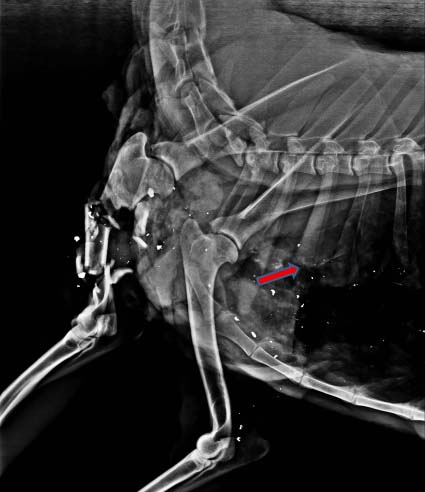

Rådjur skjutet med konventionell kula in genom vänster bog och ut bakom höger bog.

Rättigheter: SVA, SLU.